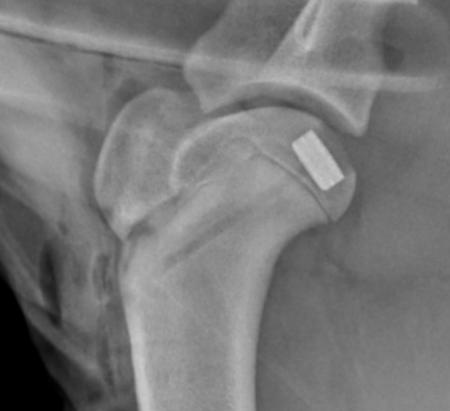

Shoulder: there is no current commercially available shoulder replacement for companion animals. The most common indication for resurfacing in the shoulder is osteochondrtitis dissecans.

Historically, we just removed large cartilage fragments arthroscopically. Most of these patients did fairly well, but a significant amount still limped or developed osteoarthritis. Now, most patients with large OCD lesions will get a Synacart or OATs resurfacing. We have seen an excellent return to high level function in most of these patients. Persistent lameness or implant infection are the most common complications.